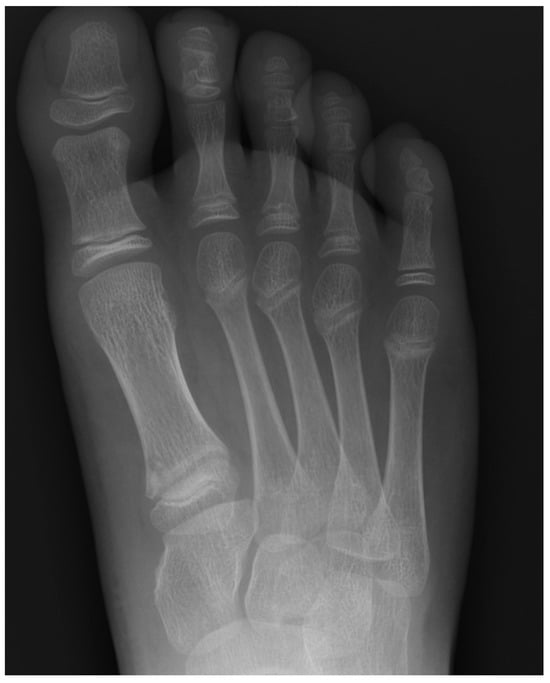

Plain radiographs are the cornerstone of imaging in the diagnosis of lesser metatarsal osteochondrosis. In the early stages of the disease, when supported by a suggestive clinical presentation, obtaining a comparative radiograph of the contralateral foot can be a useful diagnostic tool (Figure 9).

Figure 9.

Radiograph of a symptomatic 10-year-old female patient showing early sclerosis and flattening of the second metatarsal head on the left foot, compared to the contralateral side.

In the later stages, radiographs may reveal characteristic changes including subchondral sclerosis, fragmentation, and flattening of the affected metatarsal head (Figure 10 and Figure 11). In some cases, the presence of joint space narrowing or bony irregularities may also be observed. However, early changes, such as bone marrow edema or subtle cartilage damage, may not be visible on standard radiographs. MRI is particularly useful in the early stages of the disease, as it can detect bone marrow edema, which is a sign of active bone inflammation and necrosis, even before structural changes become apparent on radiographs (Figure 10, Figure 11 and Figure 12).

Figure 10.

Radiograph (left) and MRI (right) of a 17-year-old female patient showing necrotic changes and initial flattening of the second metatarsal head.

Figure 11.

Radiograph (left) and MRI (right) of a 15-year-old male patient with osteochondrosis of the third metatarsal head and early signs of deformation.